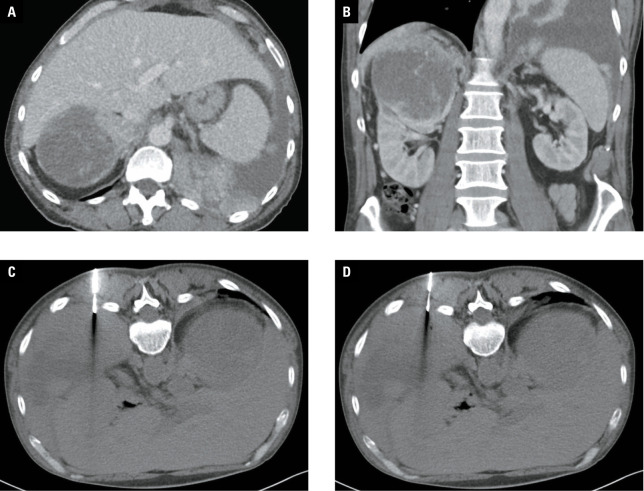

Materials and methods: A total of 138 percutaneous biopsies for tumors ranging from 21 to 133 mm in diameter (median, 72 mm) were carried out in 134 patients with suspected mRCC over a 5‑year period. The biopsy location was variable, with kidney biopsy performed in 77 cases (55.8%), and other localizations (retroperitoneum, peritoneal cavity, liver, pelvis, pleural space, lung, mediastinum, chest or abdominal wall, and pancreas) in 61 cases (44.2%).

Results: As many as 288 biopsies (97.1%), yielded truepositive results, and 4 procedures (2.9%) yielded histologically falsenegative results that required confirmation through extended rebiopsy. RCC was the most common individual diagnosis (85.5%), with non‑RCC histology verified in 14.5% of cases. In total, 32 complications (23.2%) were confirmed, 2 of which were pneumothoraces, 29 were minor bleeding that needed only conservative management, and 1 case required angiography and embolization for hemorrhage treatment. While no significant relationship between the biopsy success and lesion localization (renal vs other) was found (P = 0.13), the relationship between complication rate and biopsy localization (renal vs other) was significant (P = 0.01).

Abstract Image